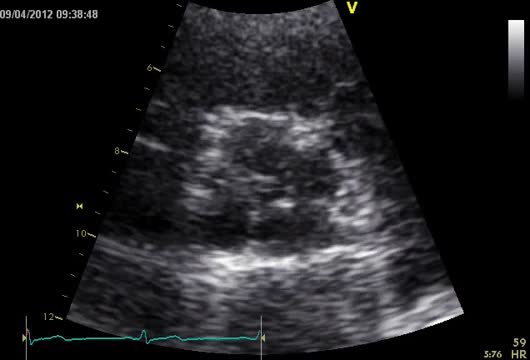

She was in sinus rhythm (∼80 bpm) with a diastolic murmur at the apex. The chest X-ray was normal with preserved cardiothoracic index. The preoperative echocardiogram revealed slightly enlarged left chambers (left atrium 46 mm; left ventricular systolic/diastolic diameters 41/59 mm; interventricular septal systolic/diastolic dimensions 11/15 mm, respectively) and preserved contractility (ejection fraction 63%). The aortic valve had four leaflets with preserved opening (no transvalvular gradient was present) but poor coaptation causing severe aortic regurgitation (vena contracta 8 mm) (Figure 1 and Video 1). The ascending aorta measured 36 mm.